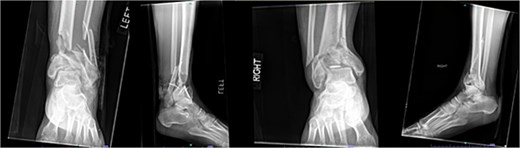

A 38-year-old male with a BMI of 27.5 kg/m2 and a history of alcohol use disorder, paranoid schizophrenia, smoking, and prior bilateral calcaneal fractures treated with ORIF 4 years earlier sustained bilateral pilon fractures after jumping from a third-story window (Fig. 3). He presented to the hospital 5 days after injury.

AP and oblique radiographs of patient 2 obtained after a fall, demonstrating bilateral pilon fractures and retained hardware from prior bilateral calcaneal ORIF.